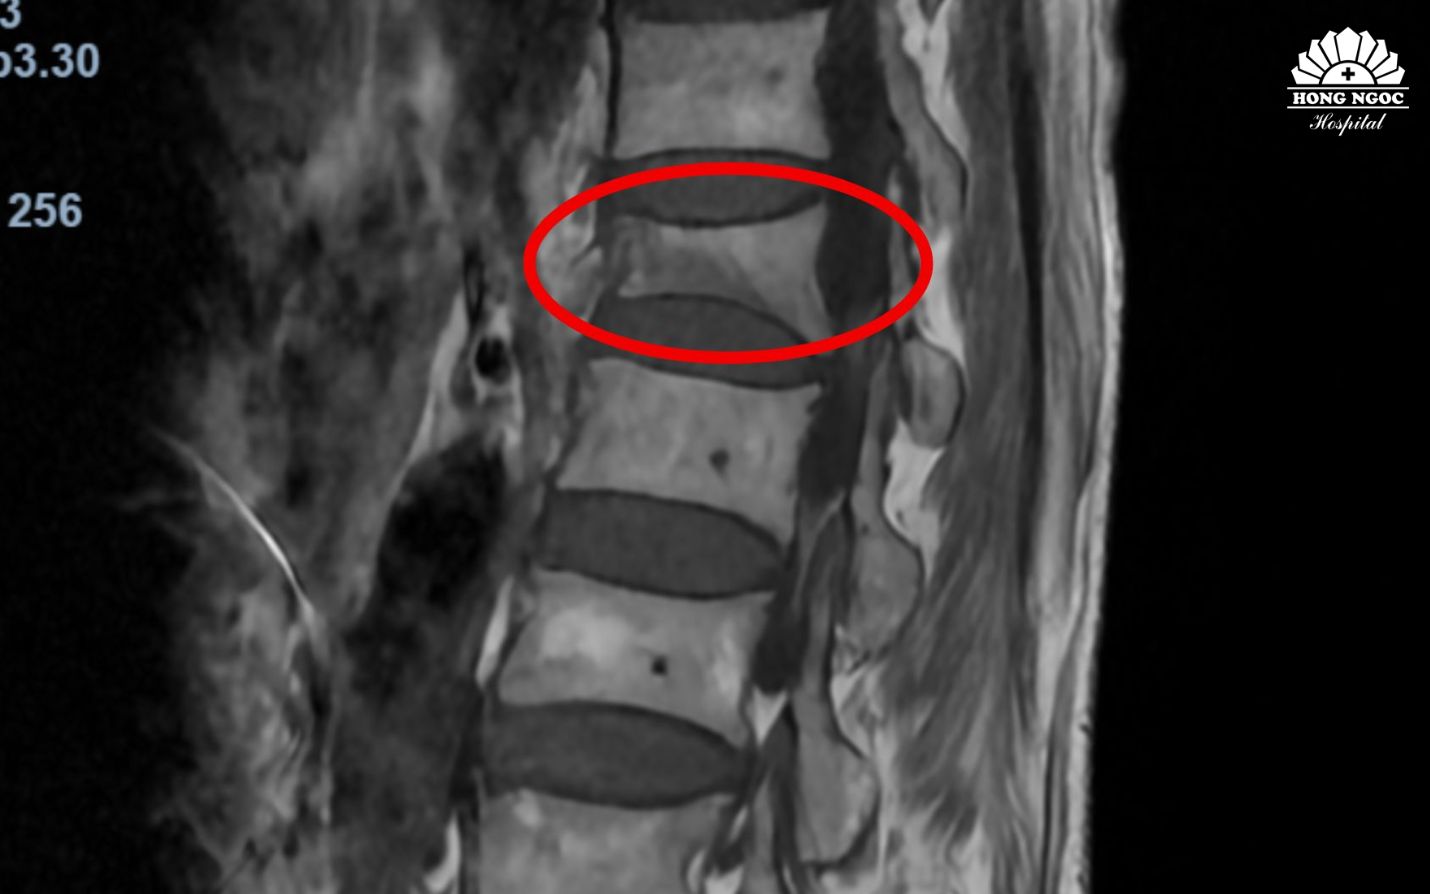

Phim chụp MRI đốt sống L1 bi xẹp khiến bệnh nhân đau lưng, mất vận động

Qua khai thác bệnh sử và chẩn đoán trên phim chụp MRI - TS.BS Trịnh Tú Tâm (Trưởng khoa Chẩn đoán hình ảnh và Điện quang can thiệp BVĐK Hồng Ngọc - Phúc Trường Minh) cho biết: “Bệnh nhân lớn tuổi, kết hợp tiền sử mắc Lupus ban đỏ mạn tính phải sử dụng thuốc điều trị trong nhiều năm khiến mật độ xương giảm mạnh, dẫn tới tình trạng loãng xương nặng, mất vững cấu trúc cột sống. Do đó, chỉ 1 động tác kéo tay nhẹ của cháu bé cũng khiến đốt sống bị lún xẹp”.